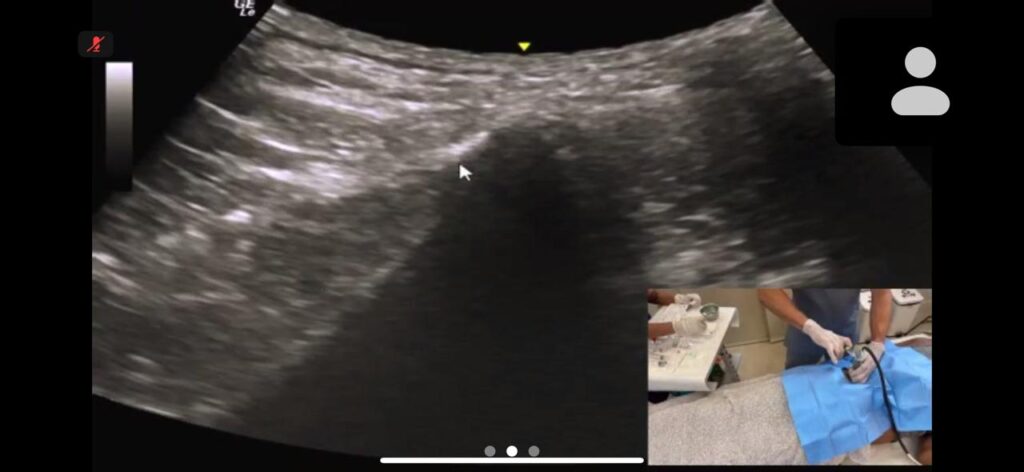

Esse concentrado é então utilizado no tratamento da lesão, com aplicação guiada por imagem para maior precisão.